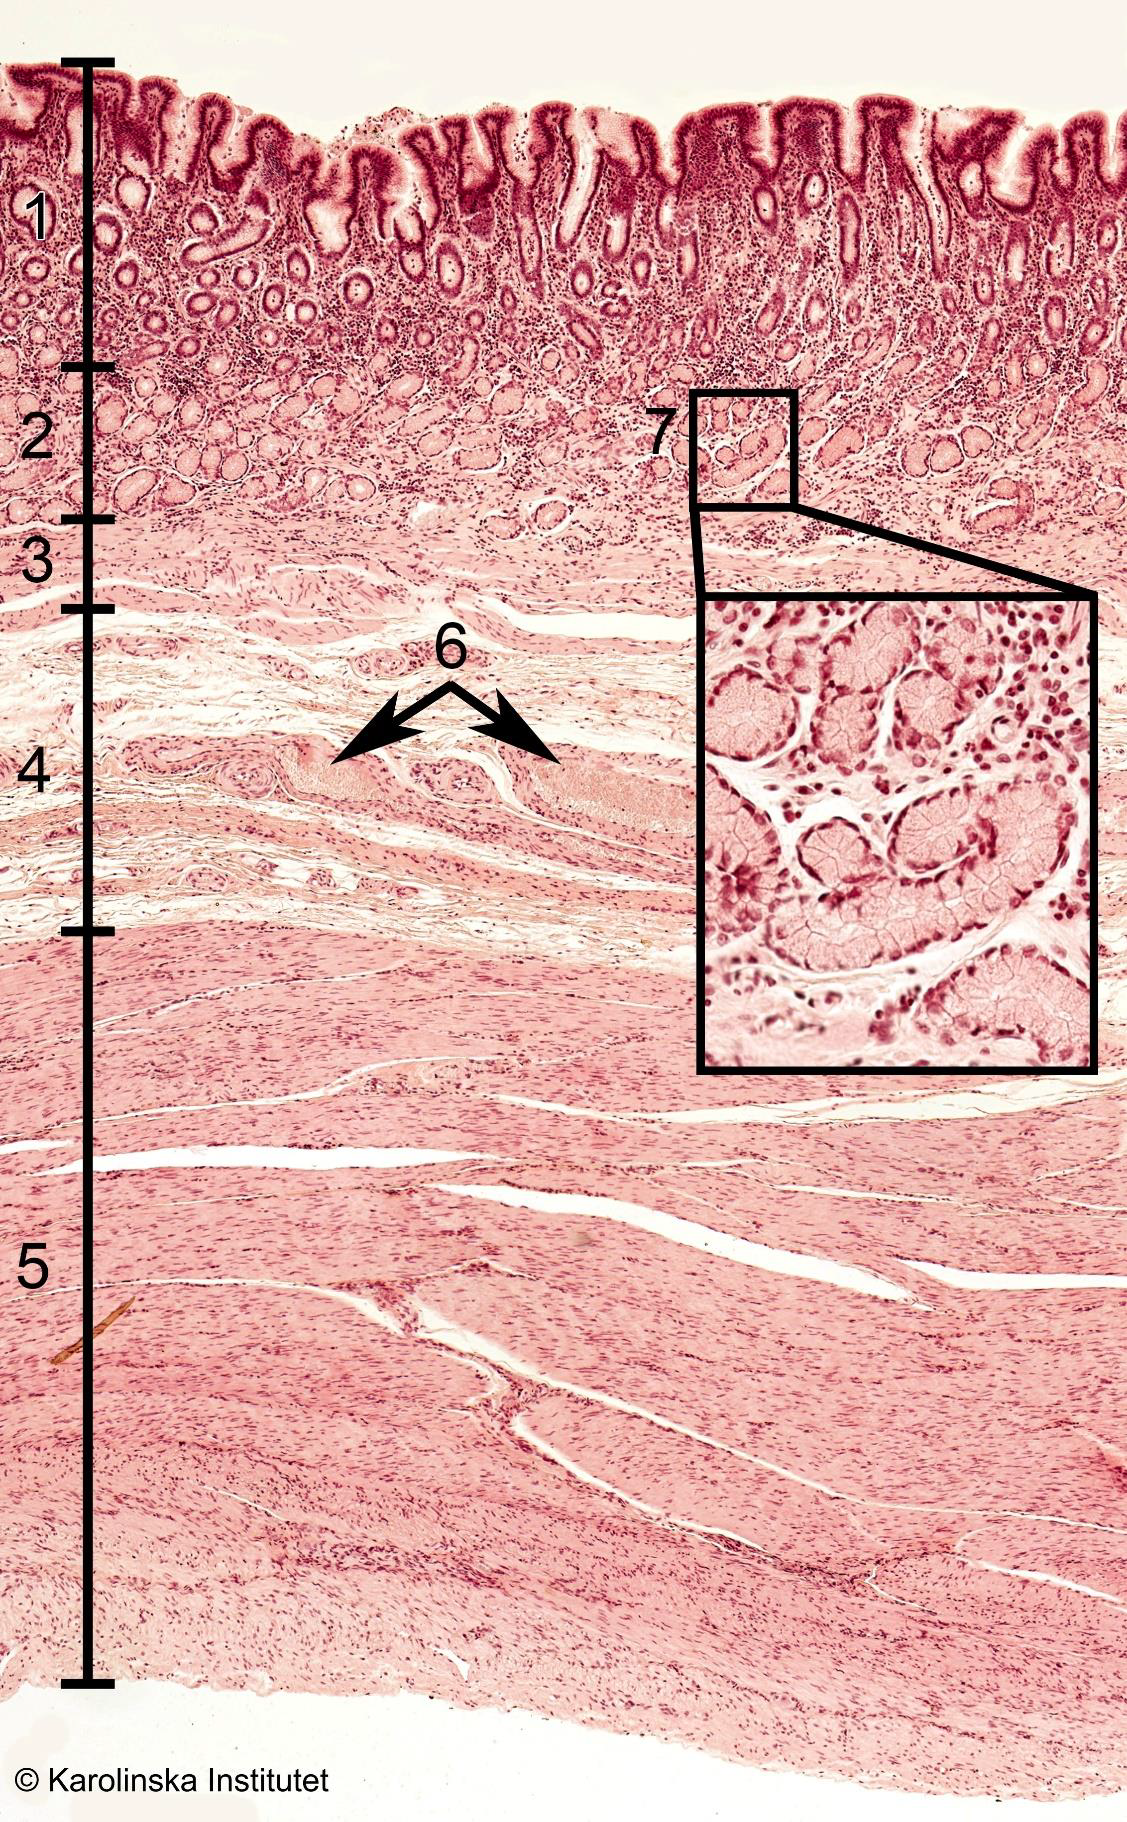

1

2

3

4

51. Mucosa,

2. Submucosa,

3. Muscularis,

4. Fibrosa,

6. Parietal cell,Stomach